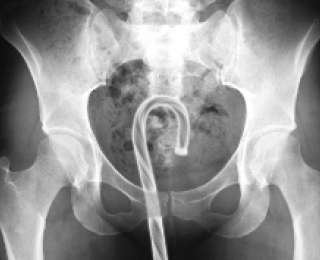

Прямая кишка:

Ручка

Карандаш

Бутылка шампуня

Бутылка ликера

Бутылка лосьона

Банка содовой

Пластиковая бутылка

Фонарик

Дверная ручка

Рюмка

Носок

Кусок карниза

Пульт управления телевизором (с полным погружением)

Вибратор

Батарейка

"Большой фиолетовый фалоимитатор" (неоднократно встречающаяся заметка)

Ложка + фалоимитатор

Игрушечная подводная лодка

2 куска мыла

Бильярдный шар

Модель ракеты